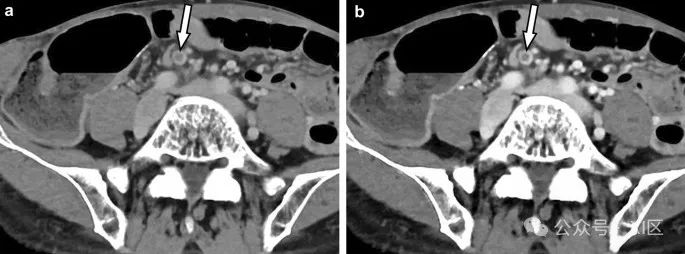

导管内乳头状黏液性肿瘤是最常见的胰腺囊性肿瘤。对导管内乳头状黏液性肿瘤的关注增加是由于其独特的恶性进展特征。光子计数CT比传统能量积分探测器CT检测到更多的胰腺囊肿。福冈共识提出了两级标准来预测导管内乳头状黏液性肿瘤的恶性,“高风险标志”和“担忧特征”。对于具有阻塞性黄疸、增强的壁结节和主导管扩张≥10 mm的“高风险标志”的患者,建议立即手术切除。因此,准确评估成像上的这些发现是必要的。光子计数CT成像在小结构如增强的壁结节的准确评估中可能特别有用(图9)。

图9 胰腺尾部的囊性病变伴壁结节(箭头)在胰腺实质期(动脉期)光子计数CT图像上分别在70 keV(A)和50 keV(B)可见。囊性病变与导管内乳头状黏液性肿瘤一致。50 keV图像(B)显示壁结节的增强比70 keV图像(A)更清晰。这种结节是恶性(即高风险标志)的标志。血管成像